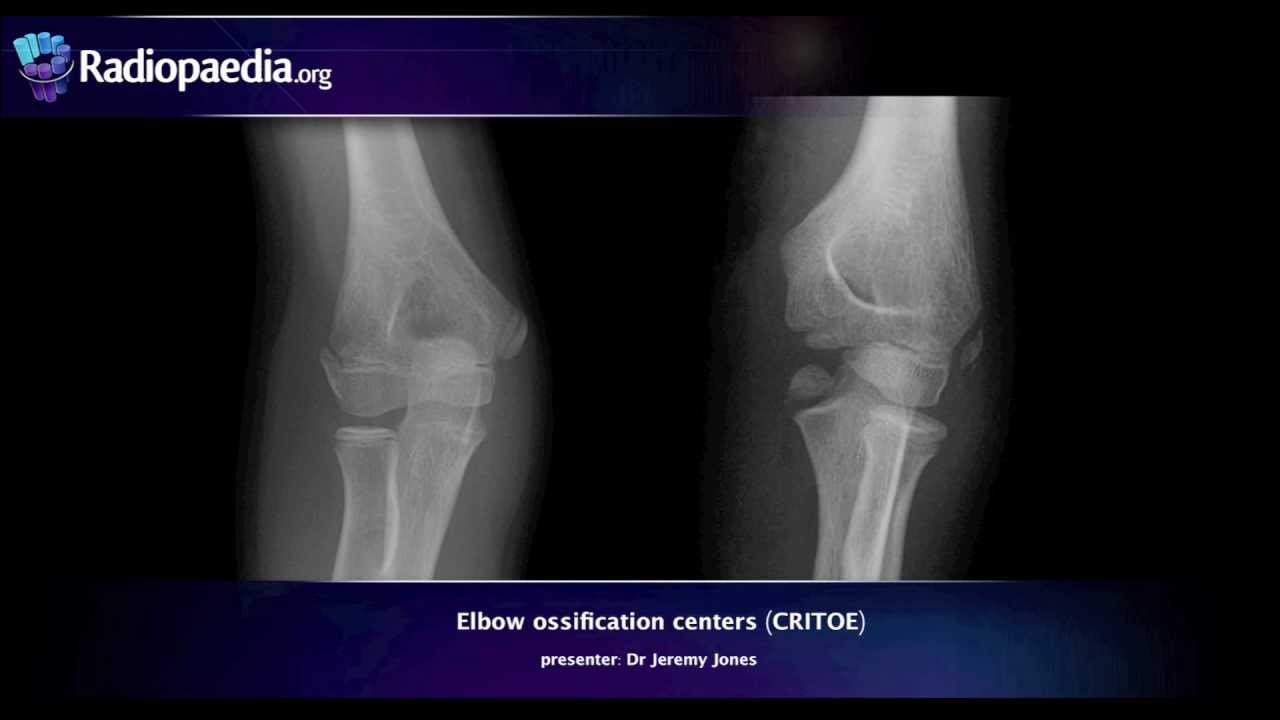

AP Você não vai es tirar né esticar o cotovelo da criança que esteja com trauma n você pode piorar a fratura piorar a lesão Então você vai fazer mais ou menos e como for possível mas o perfil é fundamental que ele esteja na posição correta aqui um pouquinho da anatomia nós temos então o úmero na na na visualização em ap né na projeção em AP Você tem o número o o rádio e a una e os centros de ossificação os centros de ossificação eles têm uma sequência correta que eles acontecem na criança então primeiro é

o capítulo depois é a cabeça do rádio depois é o epicôndilo Medial depois a troca depois o olécrano o olécrano é muito melhor de ver nesta posição né no perfil Então veja aqui úmero rádio né a cabeça do rádio una olécrano esta posição está perfeita esse posicionamento está perfeito aqui 90º e você vê essa imagem aqui que parece um oito então quando você vê essa imagem parecendo um oito tá significa aí que o posicionamento está perfeito e para avaliação aqui no perfil nós vamos prestar atenção em algumas coisas primeiro acompanhar o córtex de todas as

os núcleos de ossificação né eles variam muito com a idade eh eles variam com o sexo é masculino feminino mas a sequência de aparecimento e de fusão deles é sempre a mesma então primeiro aqui o capítulo depois a cabeça do rádio daí aqui O epicôndilo interno ou Medial daí a tró depois o olécrano o olécrano que é melhor visto no perfil e por último o epicôndilo externo ou lateral Então existe várias formas de se memorizar essa sequência né uma delas é memorizando esse nome que são as iniciais aí ah Existem várias outras mas você deve

memorizar você deve escolher uma forma então primeiro este depois este depois aquele aqui aqui e aqui então vamos ver aqui alguns cotovelos em idades diferentes neste caso aqui o úmero o rádio a una e o único centro de ossificação aqui presente é o capítulo então uma criança por volta aí de 1 ou 2 anos de idade então aqui uma criança já mais velha nós temos então o úmero o rádio e a una né o capítulo a cabeça do rádio e o epicôndilo Medial ou interno né Nós não temos ainda da tró nós não temos ainda

do olécrano nem do epicôndilo lateral então aí uma criança por volta de 6 7 8 anos por aí nesse outro caso uma criança mais velha nós temos então o capítulo a cabeça do rádio O epicôndilo interno ou Medial a troca o o tá ali que tá aqui e o epicôndilo lateral ou externo e agora vamos às linhas então a linha do córtex anterior do úmero ela tem que cruzar aqui no meio do capítulo E aí depois você vai passar a linha do rádio que também tem que cruzar no meio do capítulo aqui a linha do